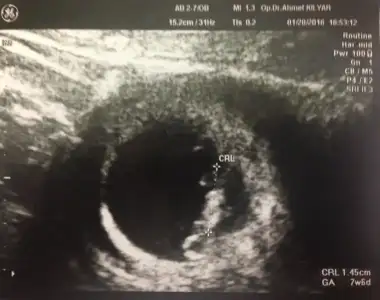

8+5 hafta ama usg ölçümü 7+6 dedi geriden geliyormuş

image.webp